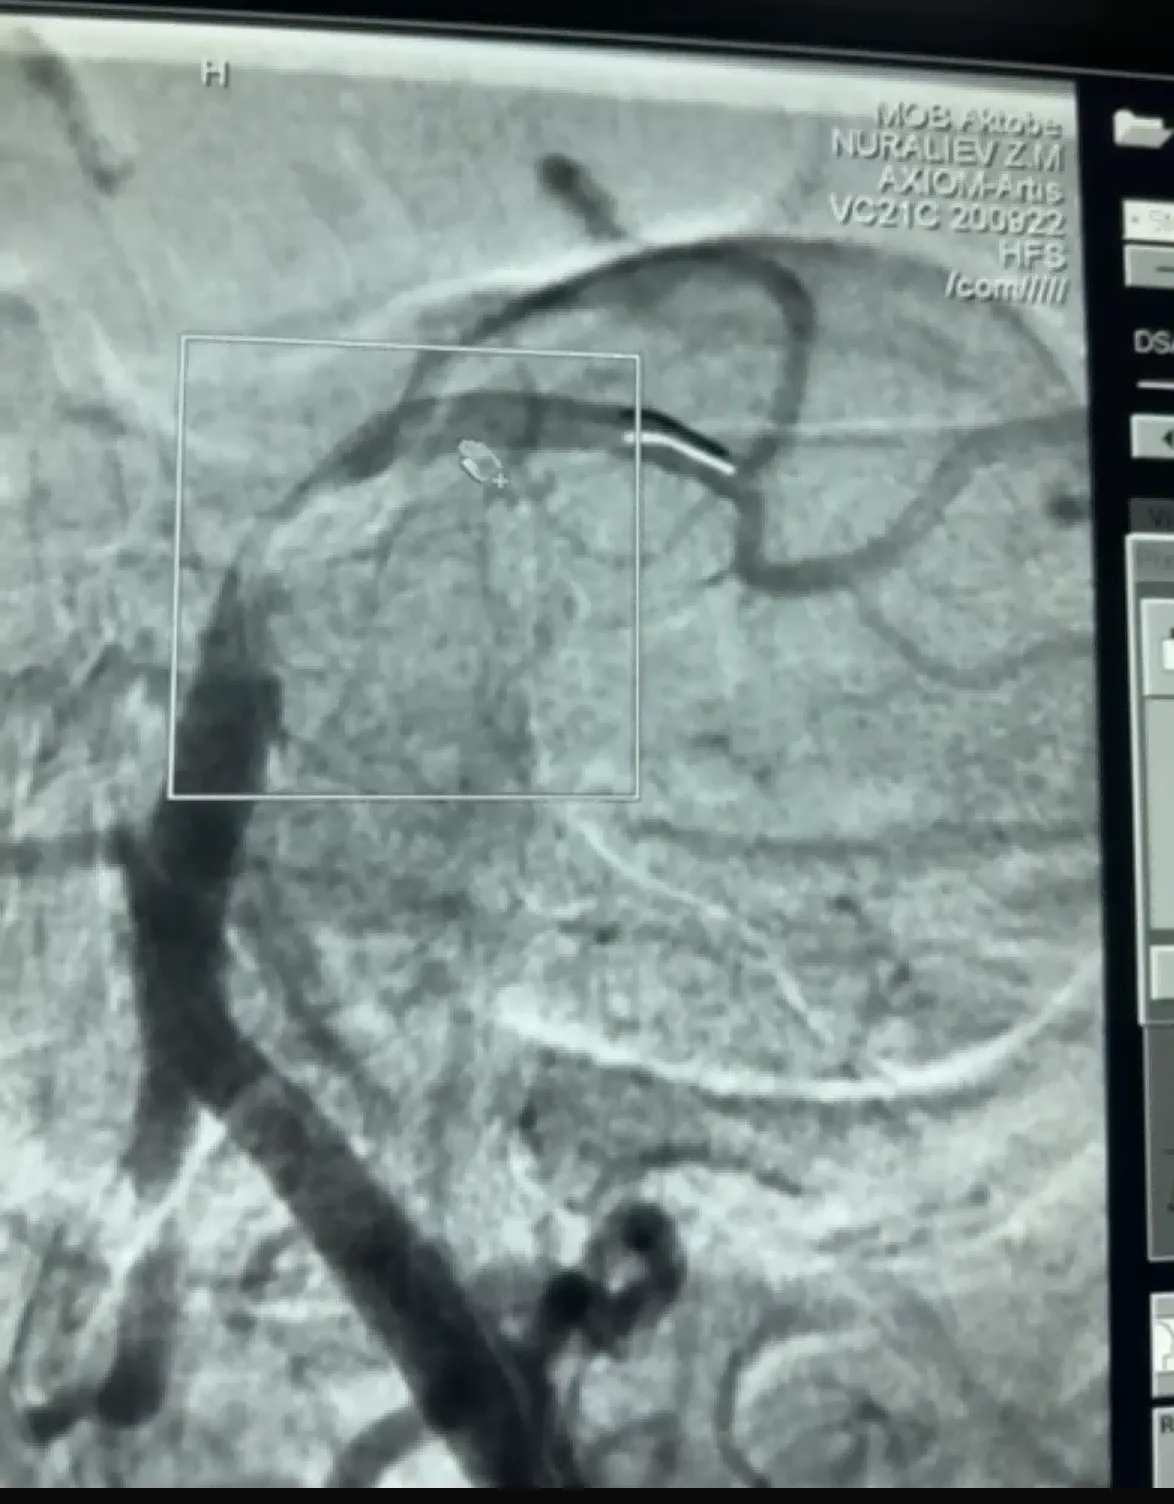

Niedawno miał miejsce udany przypadek trombektomii z użyciem urządzenia Dredger Stent Retriever firmy NeuroSafe Medical Co., Ltd. Urządzenie Dredger Stent Retriever ma nieinwazyjną, miękką końcówkę, która znacznie zmniejsza ryzyko uszkodzenia błony wewnętrznej, a także specjalny kształt otworu, który wychwytuje skrzepy krwi głównie poprzez zaciskanie zmian szczeliny.